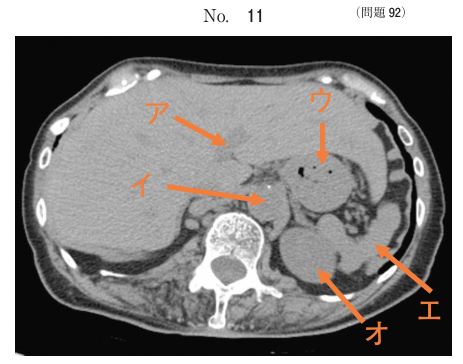

午前/問題92

腹部CT像別冊No. 11 を別に示す。正しい組合せはどれか。

1.ア ーーーーー 肝静脈

2.イ ーーーーー 下大静脈

3.ウ ーーーーー 胃

4.エ ーーーーー 膵臓

5.オ ーーーーー 脾臓